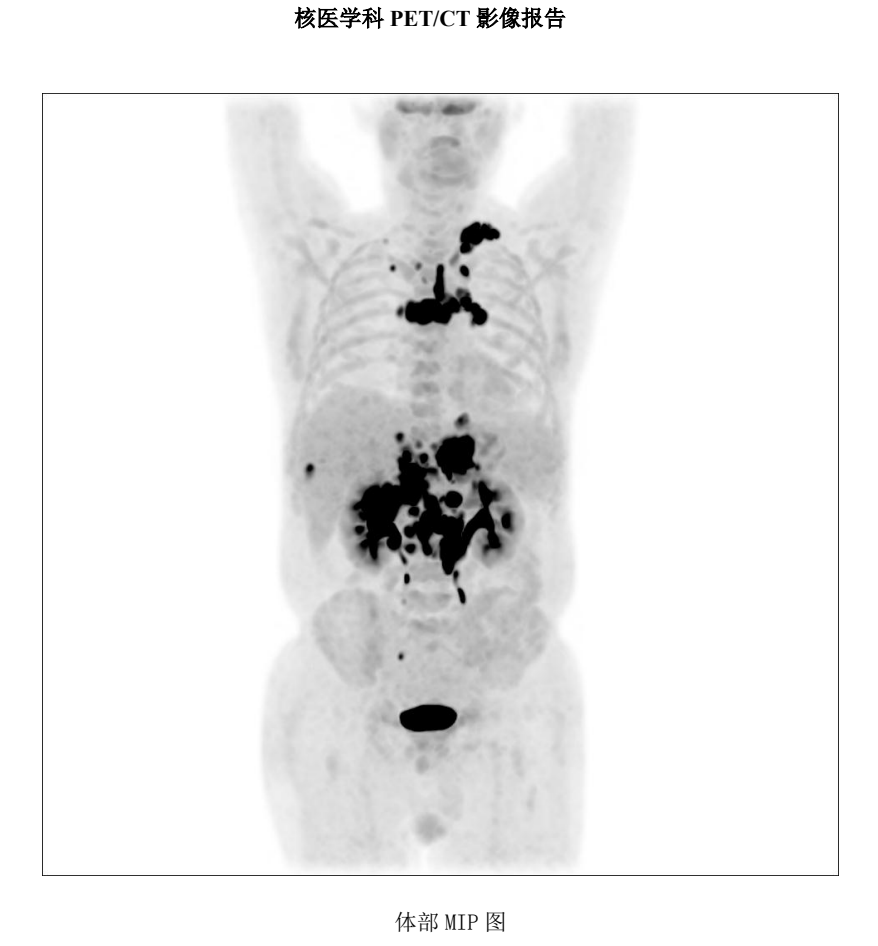

再次对病灶进行活检,结果显示CD19(-)、CD20(-)、CD22(弱 +) 。面对这一结果,治疗似乎陷入了僵局,靶点几乎全部缺失,接下来该如何应对?最终,主任决定更换细胞制备公司,并采用CD19、CD20、CD22三靶点CAR-T疗法进行治疗。结果显示,CD20-CAR-T细胞扩增良好,而CD19、CD22靶点未见明显扩增。

2025 年 2 月,PET-CT 评估显示完全缓解(CR) ,Deauville 评分为 1 分(提示无肿瘤活性),全家喜极而泣!

然而,我们仍不敢掉以轻心,继续采用口服西达本胺进行维持治疗。从结果看,这次的CR极有可能是来自于CD20靶点CAR-T的作用,CD19,CD22在丢失表达的肿瘤这里失去了抗原的刺激,没法识别到肿瘤了,而CD20这个靶点意外的扩增是个没想到的结果,原来细胞公司表示在先前研究中,也遇到过肿瘤细胞CD20表达丢失的情况,但是他们CAR-T成功扩增的结果,然而单独一个CD20靶点的CAR-T细胞扩增能否长期持续缓解呢?我们内心都是打鼓,不踏实的。